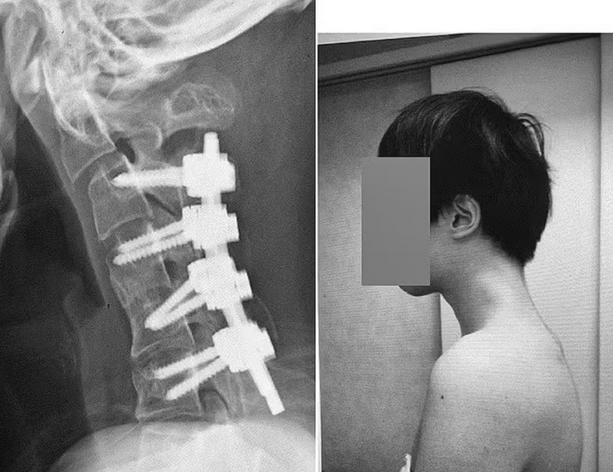

Japon: Trop sur son téléphone, il ne peut plus relever la tête

On savait que passer trop de temps sur son téléphone n’était pas recommandé pour la santé (et l’onanisme ?), mais on était loin de s’imaginer que cela pouvait avoir un tel impact sur le corps…

Les images sont terrifiantes, mais la mésaventure vécue par ce jeune Japonais est bien réelle. Après avoir passé des années à jouer à des jeux vidéo sur son smartphone, il lui est devenu impossible de relever la tête. Il avait développé ce que les médecins appellent un «syndrome de la tête tombante», comme l’explique leur rapport, cité par le «Daily Mail».

Enfant, tout allait bien pour ce Japonais âgé aujourd’hui de 25 ans. Mais arrivé à l’adolescence, il subit un harcèlement scolaire intense qui le mène à s’isoler. Il abandonne l’école et passe des années barricadé dans sa chambre où il s’adonne à de longues sessions de jeux vidéo sur son téléphone portable. Or, pour regarder son téléphone, il prend l’habitude de plier son cou pendant des heures.

Au bout d’un moment, le jeune homme a développé des douleurs dans la nuque et réalise qu’il n’arrive plus à relever la tête. Ce qui lui cause par ailleurs des problèmes pour avaler ses repas. Il se décide alors à consulter un médecin.

Des vertèbres déformées et disloquées

On lui diagnostique alors un «dropped head syndrome» ou «syndrome de la tête tombante». À force de pencher la tête continuellement pour fixer son téléphone, les vertèbres de son cou s’étaient déformées et disloquées. De plus, un tissu cicatriciel s’était développé dans sa colonne vertébrale.

Heureusement, tout s’est bien terminé pour le jeune homme. Une intervention chirurgicale a permis aux médecins de retirer les vertèbres endommagées ainsi que le tissu cicatriciel accumulé dans son cou. Le Japonais a ensuite dû vivre un certain temps avec des vis et des tiges métalliques implantées dans les os de son cou pour redresser sa posture. Après six mois, il a enfin pu relever la tête et contempler autre chose que le sol.

Si le patient souffrait probablement d’un trouble du développement sous-jacent (voir encadré), les médecins ont conclu que la position adoptée par le jeune homme pour jouer sur son téléphone avait largement participé au développement de ce terrifiant syndrome. Vous savez maintenant comment faire peur à vos ados qui passent trop de temps sur leur téléphone.

D’autres causes possibles

Le «syndrome de la tête tombante» se caractérise par une faiblesse importante des muscles du cou. Ce syndrome est le plus souvent associé à des troubles et maladies neuromusculaires, mais il peut aussi être déclenché par d’autres conditions, comme l’abus de certaines drogues.

Source: https://www.20min.ch/fr/story/japon-trop-sur-son-telephone-il-ne-peut-plus-relever-la-tete-103351051